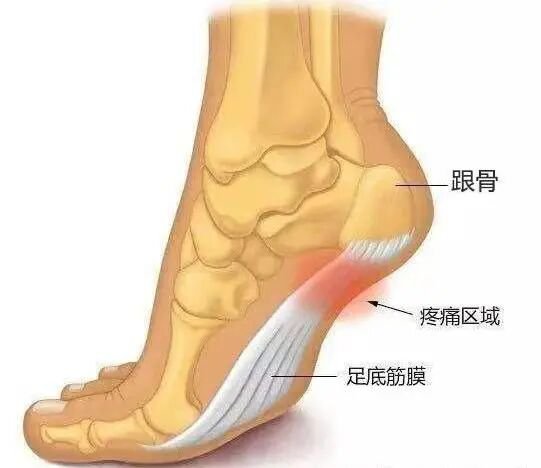

1、足底筋膜炎

正常足弓就像一张弓,足底筋膜就像弓弦,我们每走一步弓弦都会收缩伸展一次,当弓弦收缩的太频繁或拉伸太大时就会受到损伤,从而产生无菌性炎症,引发足底筋膜炎。

示意图片来源于网络,侵删